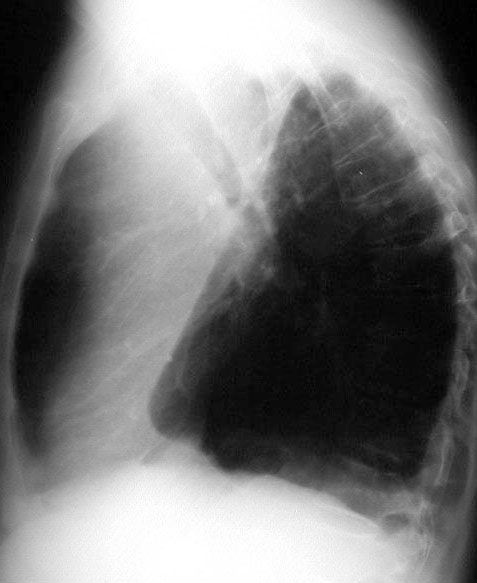

SIGNO DEL TALLE PLANO

En el colapso del lóbulo inferior izquierdo, la radiografía posteroanterior de tórax puede demostrar la desaparición de la convexidad del cono de la pulmonar al rotar el corazón ligeramente hacia una posición oblicua anterior derecha, lo que parece aplanar el contorno cardiomediastínico en el lado izquierdo (flat waist sign).

Aunque la fotografía no es óptima, existe un aumento de densidad retrocardiaco por el colapso del lóbulo inferior izquierdo.